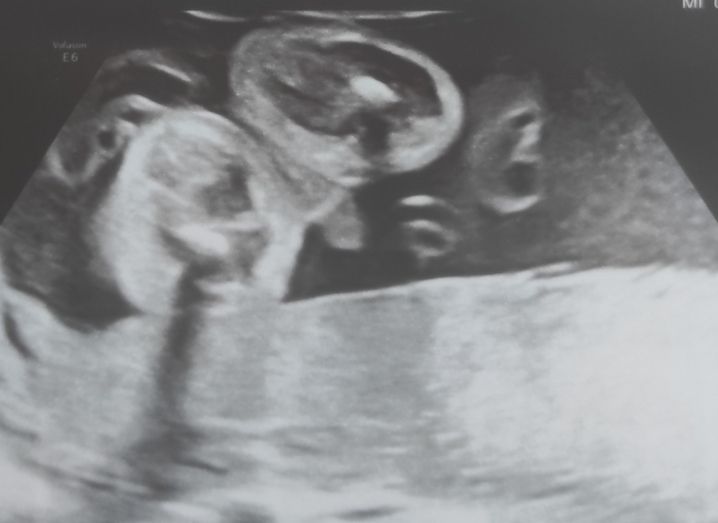

Всем привет. На 16 неделе узистка сказала, что наш малыш похож на мальчика. Мне хотелось девочку, но спокойно отнеслась, выбрали имя. И вот в 24 недели меня переклинило, не верю, что мальчик и всё тут. Пошла на УЗИ, подтвердили мальчика и показали, дали фото. А я все равно поверить не могу, наверное, гормоны накрыли.

Конечно мальчик, как можно не верить тому что на фото😀 мне три раза подтвердили и показали , и все подтвердил пгт🤷♀️ и фото такое же с причиндалом как у вас